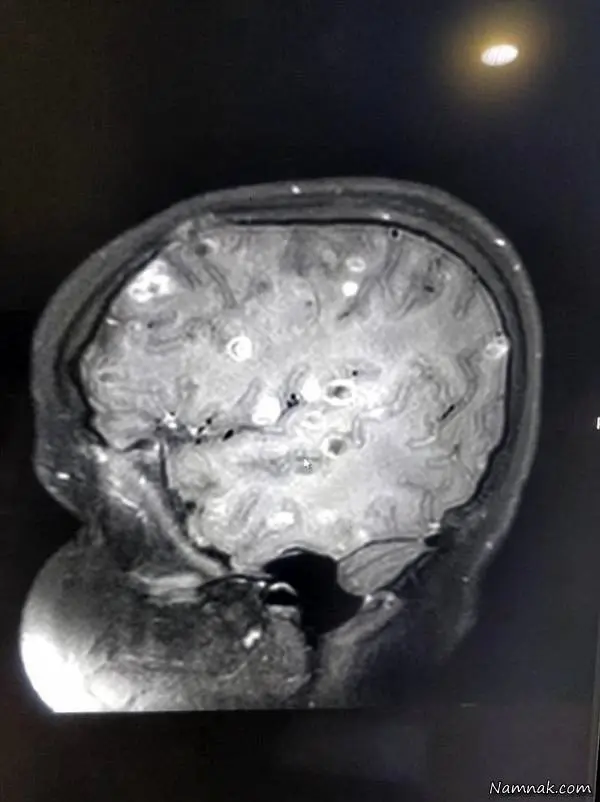

در میان اخبار عجیب و غریب روز تصاویری عجیب تر از مغز یک دختر بچه 8 ساله جلب توجه می کرد ، تصویری که در وب سایتها با تیتری رعب آور منتشر شد :"مغز دختر 8 ساله با 100 تخم کرم محاصره شد !" خبری که جزئیات و تصاویر مربوط به آن را در ادامه این بخش از نمناک خواهید خواند.رپورتاژ

دختر هشت ساله ای که نامش منتشر نشده است به دلیل وجود 100 عدد تخم کرم نواری در مغزش دچار تشنج و حملات صرع شد ؛ این دختر پس از خوردن گوشت نپخته یا میوه و سبزیجات نشسته متحمل درهای فلج کننده ای شد. این دختر از دهلی نو ، در ابتدا با دوز بالایی از استروئید تحت مداوا قرار گرفت چراکه پزشکان مشکوک به وجود کیست هایی درمغز او شدند؛ ولی به جای درمان ، دارو او را از 40 کیلو به 132 کیلو رساند؛ عوارض به حدی بود که او دیگر قادر به راه رفتن نبود و نفس نفس میزد.

شش ماه بعد ، پدر و مادر ناامید دختر، او را به بیمارستان فورتیس میبرند ، در آنجا مشخص میشود که او از بیماری خاصی به نام نورو سیستی سرکوزیس رنج می برد ؛ تصور میشد که این کرم های خوکی پس از مصرف گوشت خوک خام ، سبزیجات یا میوه نشسته ، از شکم و از طریق جریان خون به مغز او راه یافتند و طبق آنچه پیش بینی میشد وجود این تخم کرم ها موجب فلج موقت او و ناتوانی دردناکش در تنفس شده بود.